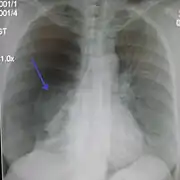

Chest X-ray

A plain chest radiograph, ideally with the X-ray beams being projected from the back (posteroanterior, or "PA"), and during maximal inspiration (holding one's breath), is the most appropriate first investigation.[30] It is not believed that routinely taking images during expiration would confer any benefit.[31] Still, they may be useful in the detection of a pneumothorax when clinical suspicion is high but yet an inspiratory radiograph appears normal.[32] Also, if the PA X-ray does not show a pneumothorax but there is a strong suspicion of one, lateral X-rays (with beams projecting from the side) may be performed, but this is not routine practice.[15][19]

Anteroposterior inspired X-ray, showing subtle left-sided pneumothorax caused by port insertion

Chest X-ray showing a pneumothorax on the right (left in the image), where the absence of lung markings indicates that there is free air inside the chest

Chest X-ray showing the features of pneumothorax on the left side of the person (right in image)

It is not unusual for the mediastinum (the structure between the lungs that contains the heart, great blood vessels, and large airways) to be shifted away from the affected lung due to the pressure differences. This is not equivalent to a tension pneumothorax, which is determined mainly by the constellation of symptoms, hypoxia, and shock.[13]

The size of the pneumothorax (i.e. the volume of air in the pleural space) can be determined with a reasonable degree of accuracy by measuring the distance between the chest wall and the lung. This is relevant to treatment, as smaller pneumothoraces may be managed differently. An air rim of 2 cm means that the pneumothorax occupies about 50% of the hemithorax.[15] British professional guidelines have traditionally stated that the measurement should be performed at the level of the hilum (where blood vessels and airways enter the lung) with 2 cm as the cutoff,[15] while American guidelines state that the measurement should be done at the apex (top) of the lung with 3 cm differentiating between a "small" and a "large" pneumothorax.[33] The latter method may overestimate the size of a pneumothorax if it is located mainly at the apex, which is a common occurrence.[15] The various methods correlate poorly but are the best easily available ways of estimating pneumothorax size.[15][19] CT scanning (see below) can provide a more accurate determination of the size of the pneumothorax, but its routine use in this setting is not recommended.[33]

Not all pneumothoraces are uniform; some only form a pocket of air in a particular place in the chest.[15] Small amounts of fluid may be noted on the chest X-ray (hydropneumothorax); this may be blood (hemopneumothorax).[13] In some cases, the only significant abnormality may be the "deep sulcus sign", in which the normally small space between the chest wall and the diaphragm appears enlarged due to the abnormal presence of fluid.[16]